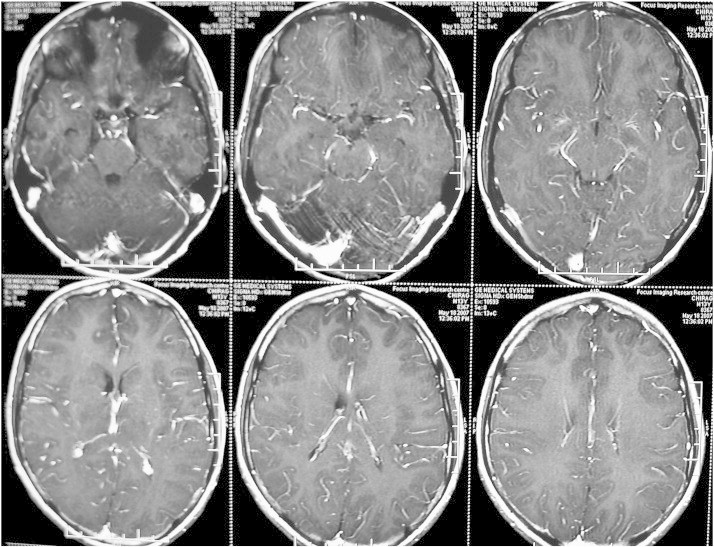

Routine investigations revealed normal hemoglobin, blood counts, blood sugar, serum electrolytes, and liver and kidney function tests. Serum calcium, phosphorous, alkaline phosphatase and thyroid function tests were normal. X-ray chest was unremarkable. Human immunodeficiency virus types 1 and 2 by ELISA were nonreactive. MRI brain revealed T1 hypointense and T2/FLAIR hyperintense lesions in pontine tegmentum, midbrain tegmentum (left > right), periaqueductal gray matter, bilateral thalamus and left lentiform nucleus, without any contrast enhancement (Figs. 2–5). MR spectroscopy through left pontine lesion showed normal NAA peak, mild elevation of choline, and no lactate peak, suggestive of a benign pathology (Fig. 6). Scalp EEG did not reveal any abnormality. On prolonged video-EEG monitoring the habitual events were recorded without any ictal correlate or any interictal discharges (Video 2).

Fig. 3.

MRI brain showing T1 hypointense and T2/FLAIR hyperintense lesions in the midbrain tegmentum (left > right), without any contrast enhancement.

Fig. 4.

MRI brain showing T1 hypointense and T2/FLAIR hyperintense lesions in the periaqueductal gray matter, without any contrast enhancement.

Fig. 5.

MRI brain showing T1 hypointense and T2/FLAIR hyperintense lesions in the bilateral thalamus and left lentiform nucleus, without any contrast enhancement.

Routine investigations revealed normal hemoglobin, blood counts, blood sugar, serum electrolytes, and liver and kidney function tests. Serum calcium, phosphorous, alkaline phosphatase and thyroid function tests were normal. X-ray chest was unremarkable. Human immunodeficiency virus types 1 and 2 by ELISA were nonreactive. Magnetic Resonance Imaging (MRI) brain revealed T1 hypointense and T2/FLAIR hyperintense lesions in pontine tegmentum, midbrain tegmentum (left > right), periaqueductal gray matter, bilateral thalamus and left lentiform nucleus, without any contrast enhancement (Figs. 2–5). Magnetic Resonance (MR) spectroscopy through left pontine lesion showed normal NAA peak, mild elevation of choline, and no lactate peak, suggestive of a benign pathology (Fig. 6). Scalp EEG did not reveal any abnormality. On prolonged video-EEG monitoring the habitual events were recorded without any ictal correlate or any interictal discharges (Video 2).